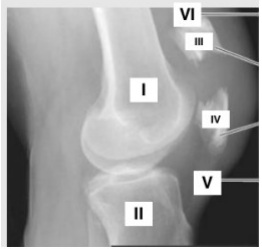

Um golpe direto na patela pode fraturá-la em dois ou mais fragmentos. As fraturas transversas da patela podem resultar de um golpe no joelho ou contração súbita do músculo quadríceps femoral. A figura a seguir representa uma radiografia em perfil do joelho após contusão, com estruturas representadas pelos números de I a VI.

Fonte: COHEN, Moisés. Tratado de ortopedia. São Paulo: Editora Roca, 2007.

Assinale a alternativa com a associação CORRETA.